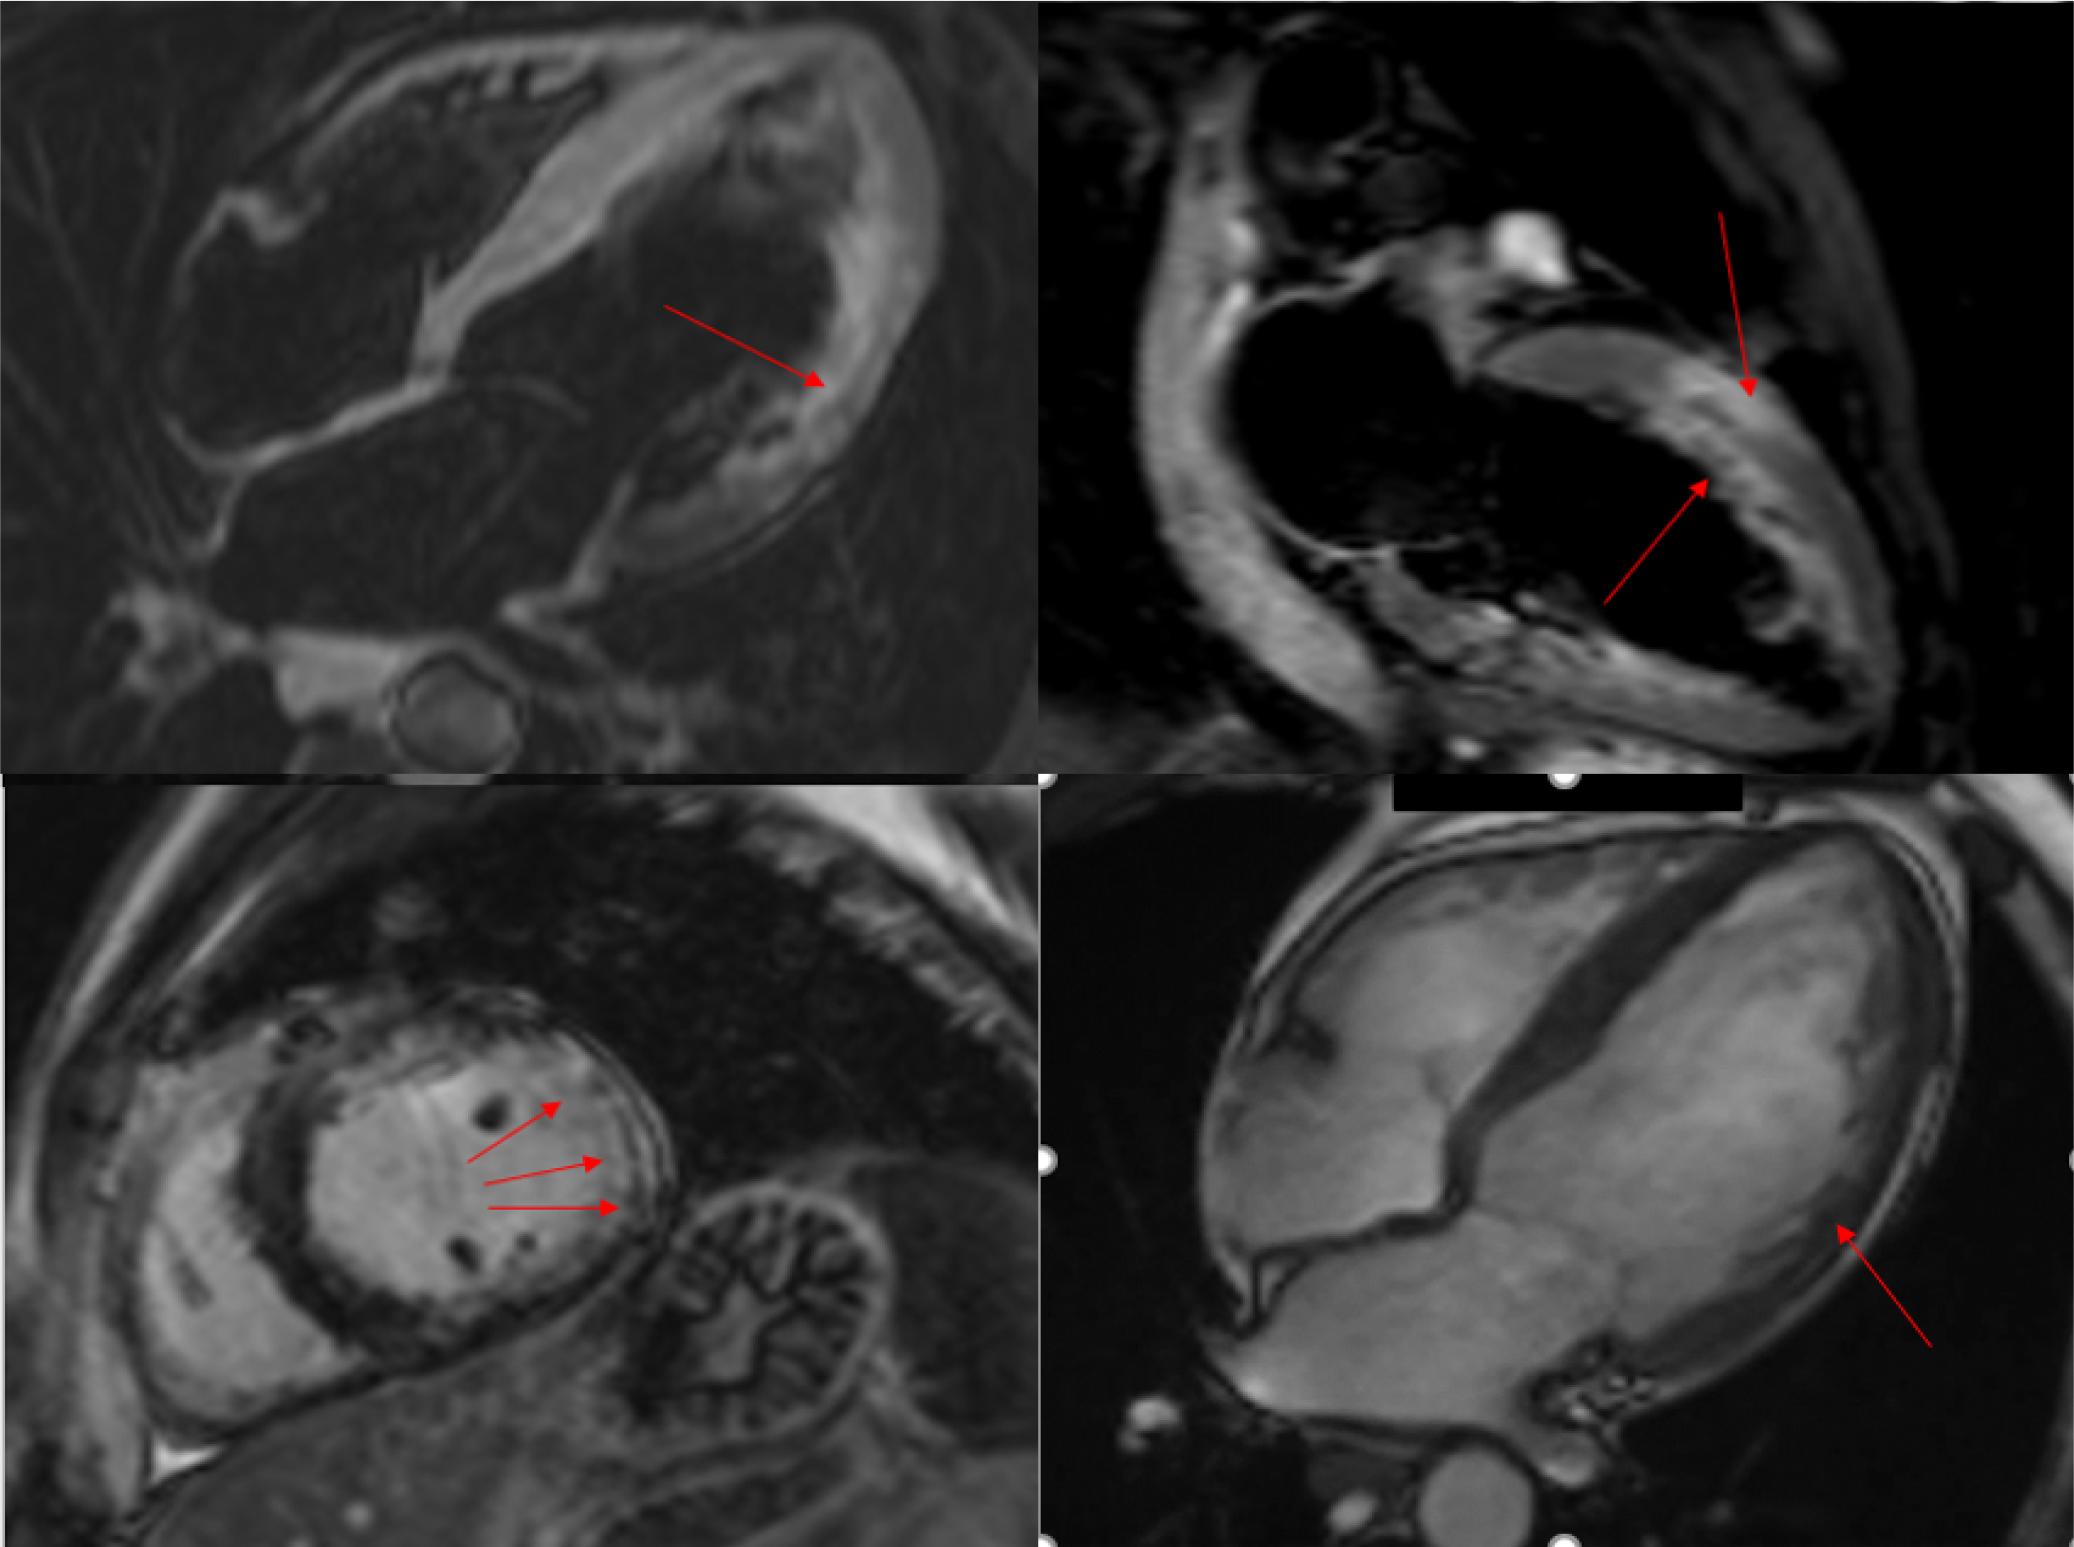

Figure 4